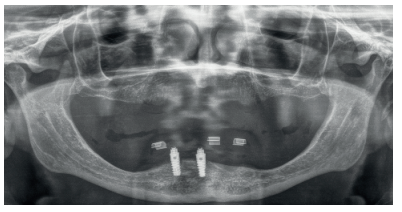

Se realiza un CBCT dental para la planificación del caso y poder rehabilitar el maxilar superior e inferior. En la mandíbula se planifica retirar los dos implantes de forma atraumática (mediante el kit de extracción a contra-torque) y la inserción de cuatro implantes para la confección de una nueva prótesis implanto-soportada. Los cortes de planificación muestran la necesidad de que los implantes insertados sean cortos y algunos de ellos, como el caso del implante en posición 44, por lingual del nervio dentario. (Figuras 5-7).

En el caso del maxilar superior, la atrofia es combinada, existiendo una gran atrofia vertical en los sectores posteriores que requiere la inserción de implantes cortos y extra-cortos, para evitar una elevación de seno a ese nivel. En las zonas anteriores (de premolar a premolar) existe una extrema reabsorción horizontal que obliga a la inserción de implantes estrechos, siendo los seleccionados cuatro implantes de plataforma reducida (3.0) y un implante de plataforma reducida Core en una zona de transición entre la atrofia anterior y posterior, que presenta una atrofia mixta (zona de 15-16) (Figuras 8-10).